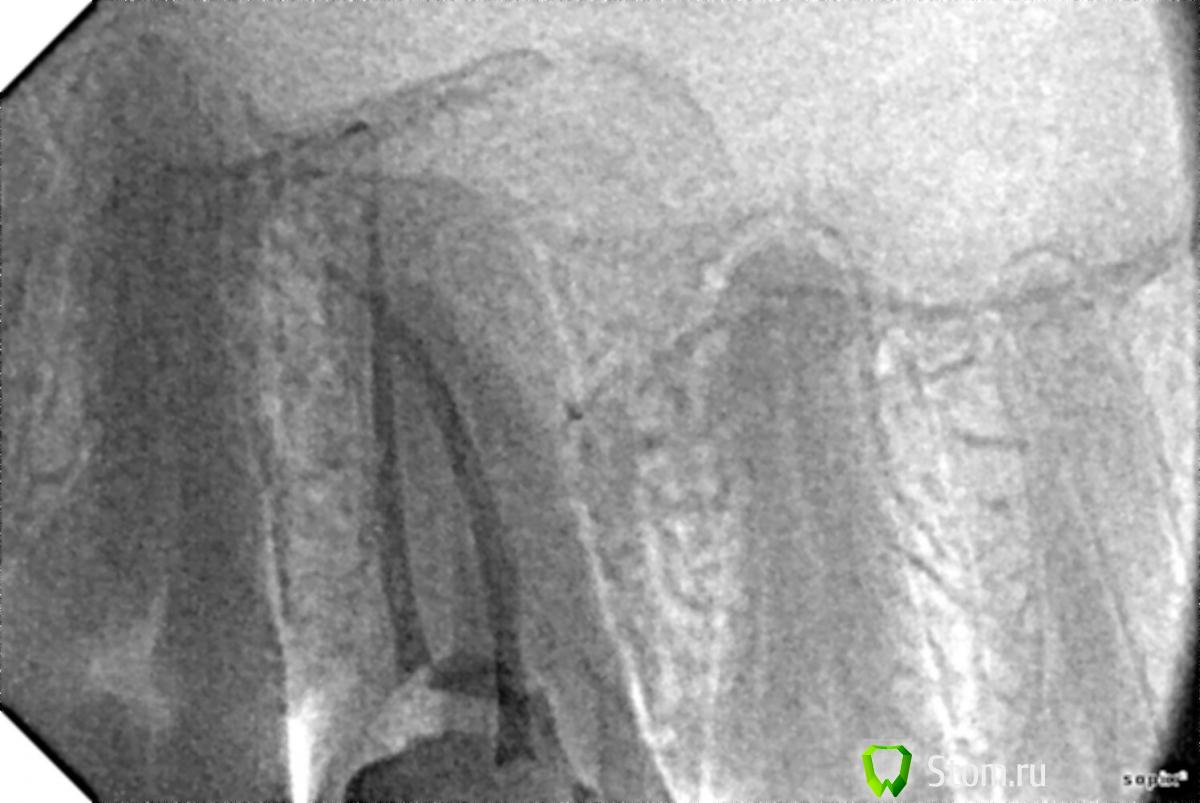

Небольшая предыстория. Несколько лет назад (точно сейчас не вспомню) в шестом верхнем правом зубе был удален нерв, а сам зуб запломбирован. Пару недель назад, при посещении стоматолога, по панорамному снимку было установлено, что каналы в этом самом зубе очень плохо запломбированы. Было принято решение зуб перелечивать. В ходе очередного приема два из трех каналов были заново запломбированы, а вот с третьим возникли трудности. Подробности точно не сформулирую, но что-то вроде "маленькое устье канала... материал вижу, но попасть сложно... необходимы специальные очки... немного кровит". В итоге доктор решил пока не трогать третий канал, поставил временную пломбу, сказал прийти через два дня на третий. А, еще предупредил о возможных болевых ощущениях при накусывании.

В течении этого дня, ночи и первой половины дня следующего, так все и было. Болезненные ощущения при накусывании, ненадолго задерживающиеся после. А вот на вторую ночь зуб начал болеть очень сильно, болел всю ночь, весь следующий день и вторую ночь. Также на вторую ночь поднялась температура до 37,5. Отека, припухлости и т.п. не наблюдалось. Когда прибежал к доктору, он сделал два снимка (их и прилагаю), удалил временную пломбу и сказал, что долечивать канал и зуб в целом следует после того как пройдет боль.

По описанной симптоматике и снимкам, по возможности, прошу консультации. А именно:

- возможные причины столь сильной боли?;

- насколько верен/профессионален/адекватен ситуации предложенный план лечения?;

- качественно ли выполнена работа по пломбировке двух каналов?

P.S. Усматривается ли на пятом зубе (по снимку справа от пломбируемого) воспалительный процесс в районе апикального отверстия?